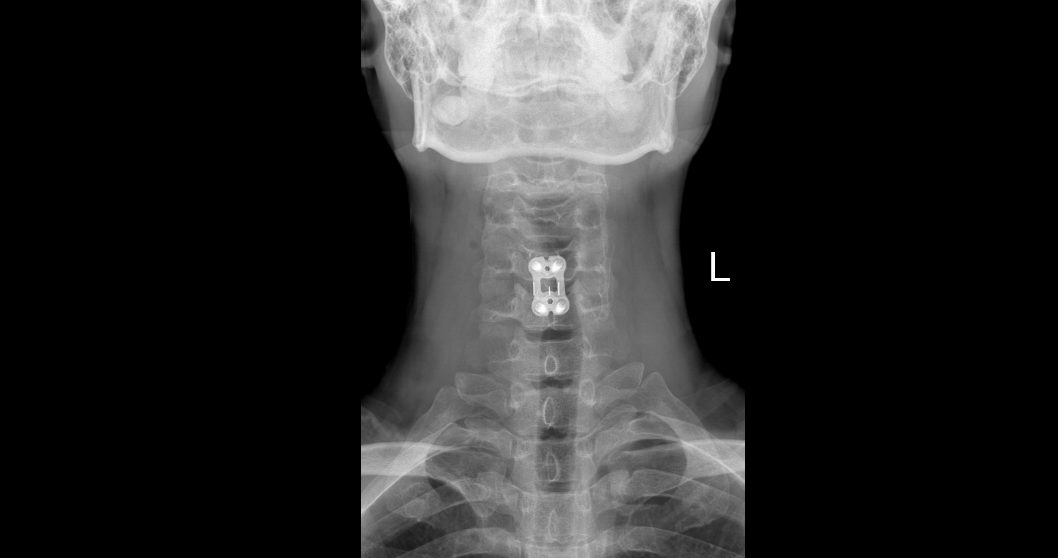

颈椎病是一种常见的疾病,主要表现为颈肩部疼痛、酸胀、僵硬、活动不畅。在大多数普通老百姓眼中,颈椎病就与颈肩部有关,但临床数据表明:一些表面...